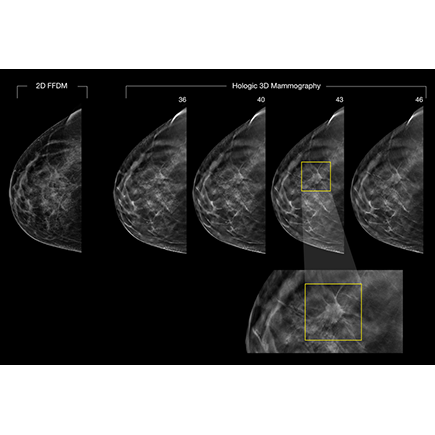

Bettering Breast Cancer Detection Rates

One key to improving breast cancer survival rates is early detection. Conventional digital mammography, produces a single image of overlapping tissue, making it hard to detect breast cancer. Hologic Inc., a maker of medical imaging systems, uses GPU-acceleration applications to enable 3D mammography, or tomosynthesis, taking multiple images of the entire breast.

Using the same scanners as conventional digital mammography, tomosynthesis allows radiologists to see through layers of dense tissue and examine the breast from every angle. The enhanced imaging offers greater ability to pinpoint abnormalities, detect tumors—while reducing false positives—and save patients from unnecessary biopsies. The GPU computing-based technique also allows for images to be processed in real time, reducing wait times for screening and diagnostic results.